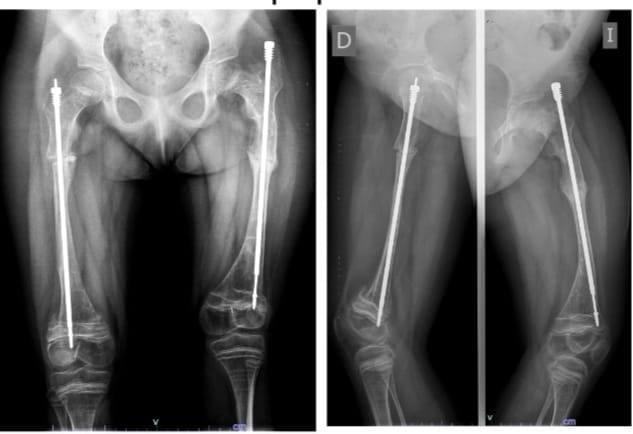

“Vino en un coche de bebé y se le práctico un tratamiento con un clavo especial, un clavo telescopado para corregir la deformidad, que se ancla en zonas seguras del hueso. Se calcula dónde tiene que ir cierto corte del hueso para recuperar el eje normal del cuerpo. El chico crece con el clavo y el clavo se elonga a medida que el chico crece”, describió.

El tratamiento de la pequeña tuvo una duración de 5 años en donde el especialista comenzó con la corrección del eje de la deformidad para luego colocar en los fémures los clavos telescopados. “Por suerte el cuerpo reacciono perfectamente, ahora vamos a comenzar los ciclos de rehabilitación despacito, pero estamos muy contentos”.

“En el rango de los 11 hasta los 13 años el índice de fractura, con el tratamiento colocado, disminuye un 60% o 70 %, pero es importante que se los proteja desde que se detecta la patología hasta que concluye su maduración”, aclaró.

“Uno intenta que los chicos tengan la mejor calidad de vida posible. Esta nena, por ejemplo, se había fracturado 17 veces ambos fémures antes de que yo la empezara a tratar, después no se fracturó más”.